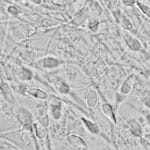

El sistema reproductor masculino es el encargado de producir, mantener y transportar los espermatozoides y el liquido que los protege, el semen. Consta de las siguientes estructuras: Pene Es el órgano que se utiliza para las relaciones sexuales y consta de tres partes diferentes: la raíz, que se adhiere a la pared del abdomen; el […]